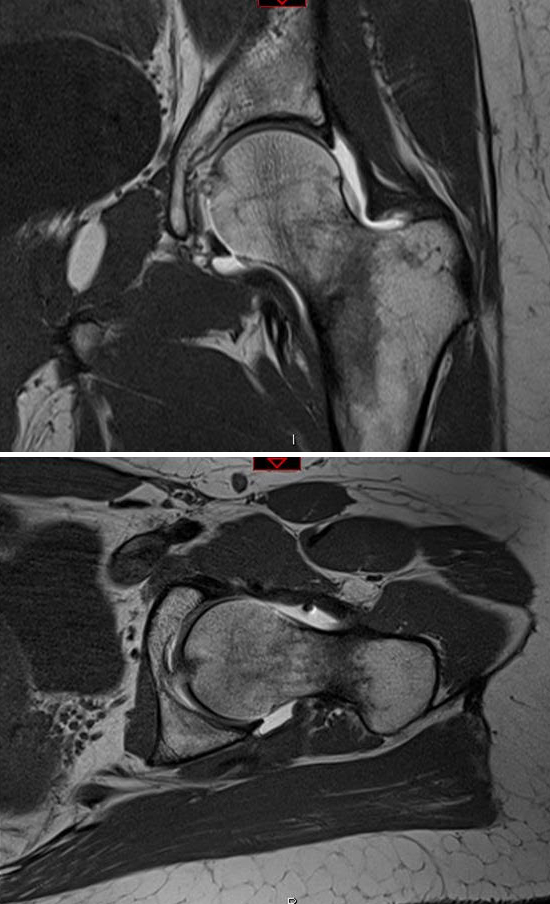

• MRI

• indications

• modality of choice when radiographs are negative

• findings

• periosteal or bone marrow edema on STIR or fat-suppressed T2

• line of decrease of intensity on T1 coronal corresponding with signal on T2 and STIR

• hip effusion

• 8x higher risk of propagation

• utility

• sensitivity 100%

• specificity 100%